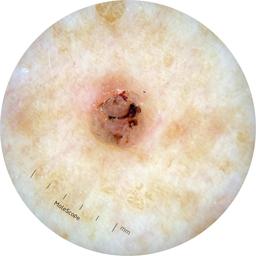

ISIC_8528385

2109 x 2109

acquisition_day 27

age_approx 60

anatom_site_1 Upper extremity

anatom_site_general upper extremity

diagnosis_1 Benign

diagnosis_confirm_type single image expert consensus

fitzpatrick_skin_type I

image_type dermoscopic